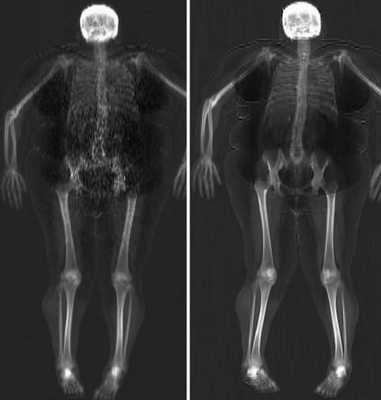

КТ ОБП. Избыточное количество висцеральной жировой клетчатки у пациента с повышенным индексом массы тела.